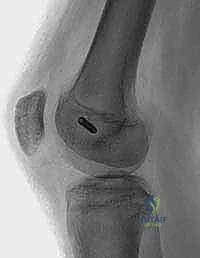

- AP, Lateral, Sunrise/Merchant Views: Essential. The sunrise view, requiring 30-45 degrees of flexion, might be delayed due to acute pain but is crucial for assessing trochlear morphology and patellar tilt.

- Limitations: Plain films can miss up to 40% of arthroscopically documented chondral or osteochondral lesions. Subtle slivers of bone can be easily overlooked.

* Nonarticular Avulsion Fracture: A less serious avulsion fracture of the MPFL off the medial patella is pathognomonic. This can appear immediately or be delayed as an ossific lesion.